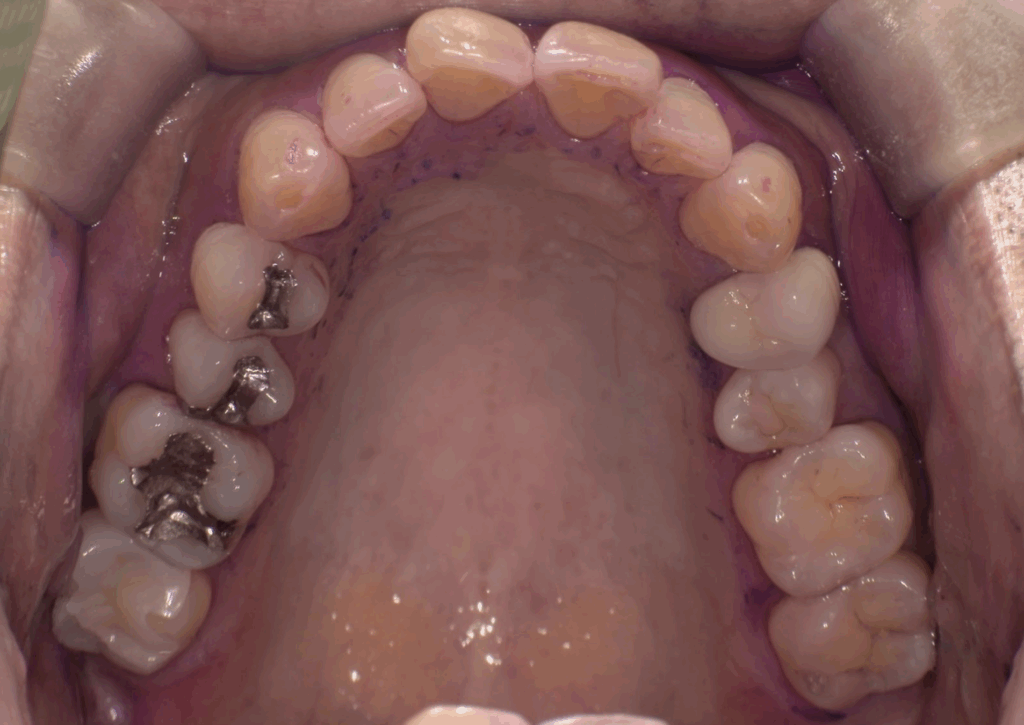

術後 右上7の銀歯がセラミックに置き換わっている(1.5時間で銀歯の除去からセラミック装着まで完了)

歯と歯の間にもう蝕があり2本同時に1日で銀歯除去からセレック置き換え治療を行った